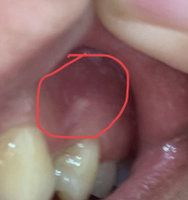

Я была сегодня у пародонтолога, который проводил чистку зубов. Врач обратила внимание, что над 4-ми, верхними, симметрично есть белые пятнышки. Сказала сразу, что это не стоматит. Сказала, что это отражение на слизистой рта моего психического состояния организма общего (сравнила как с псориазом или крапивницей). Сказала, что надо приводить общее состояние в порядок и что тогда эти пятна пройдут. Специально лечить не надо. Я ее 1000 раз переспросила, точно ли это не что-то страшное, не злокачественное. Она ответила, что точно это не страшное, просто внутреннее состояние отражается на деснах. Боюсь онкологии, начиталась ужасов в интернете. Они симметричны сверху. Вообще ничем не беспокоят. Вчера я пыталась ногтем сковырнуть это белое пятно и только поранила его и вышла кровь.

Что это за пятна? Права ли врач, что это так слизистая реагирует на стресс (сейчас принимаю антидепрессанты)?

К сожалению, по фото совершенно невозможно определить характер образования. Это может быть связано с тонкой надкостницей и близким расположением корней, а может лейкоплакия, на фоне недостатка витаминов и микроэлементов. Ковырять ногтем, определённо, не стоит. Рекомендуем Вам обратиться к терапевту для проведения повторного осмотра и оценки пятен.